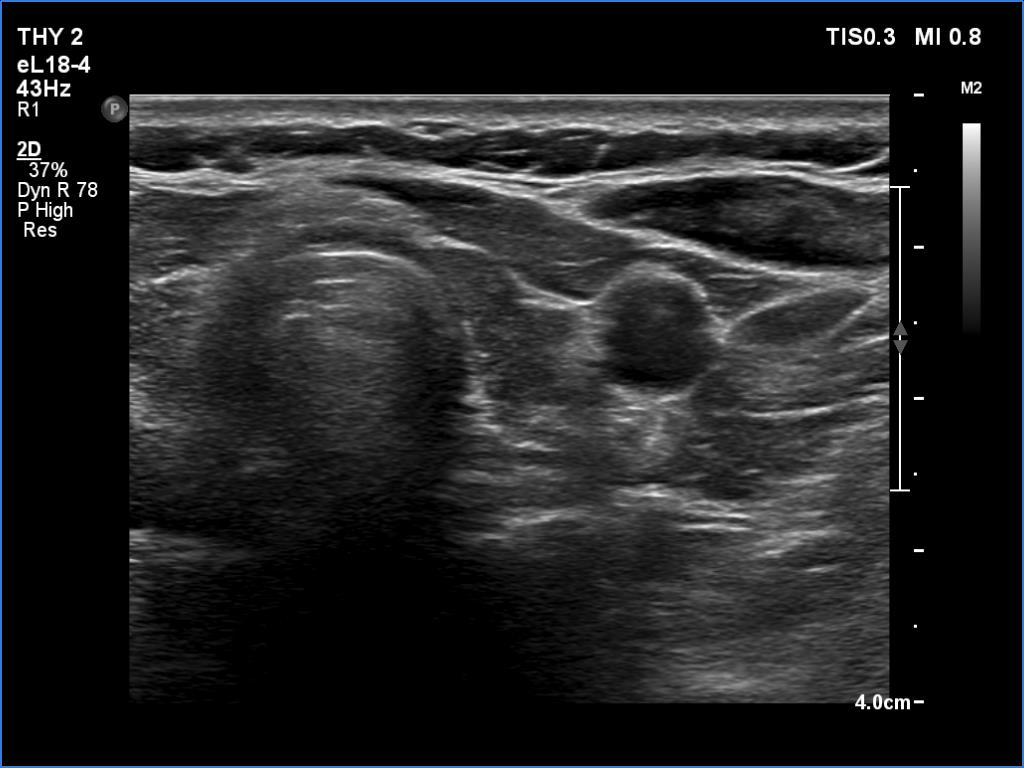

Ultrasonography. The thyroid was atrophic. Both lobes were composed of a central, larger hypoechoic area surrounded with echonormal tissue. The pattern did not correspond to nodule. The vascularity was decreased.

Comment. A central hypoechoic part surrounded with echonormal tissue is one of the typical presentations of Hashimoto's thyroiditis, not infrequently misinterpreted as a large hypoechoic nodule which occupies great part of a lobe. The irregular margins, the infiltrative borders of the thyroiditis are the main clues of differentiation this presentation from nodular goiter. The pattern can be observed usually in both lobes which is also characteristic of this form of thyroiditis.